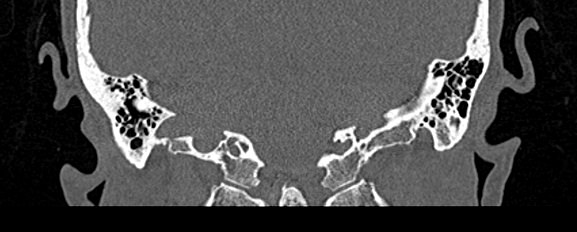

Мультиспиральная КТ позволяет детально визуализировать все вышеперечисленные анатомические структуры височных костей, диагностировать заболевания среднего и внутреннего уха.

КТ наиболее информативна при черепно-мозговых травмах, воспалительных заболеваниях уха, опухолевых процессах этой области. При компьютерной томографии возможно проследить ход барабанной перепонки, оценить структурность и положение слуховых косточек (молоточка, стремечка и наковальни), оценить объем и расположение содержимого в антральной клетке или ячейках сосцевидного отростка височной кости.

- показать четкую картину строения среднего уха.